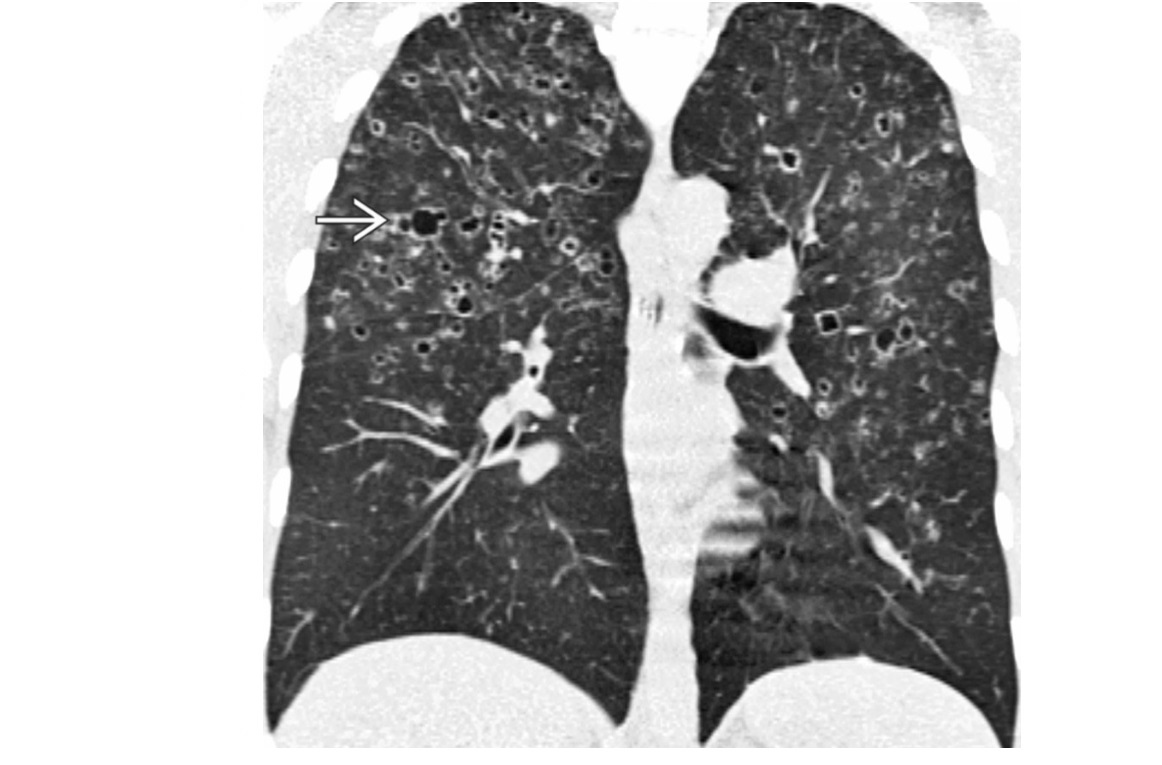

Pulmonary Langerhans cell histiocytosis (PLCH)

Predominant upper lobes

bizarre-shaped thick pulmonary cysts

Smokers

Early stages of disease, 1-10mm nodules in mid/upper zone predominant

Effusions are rare

Sparing costophrenic angles